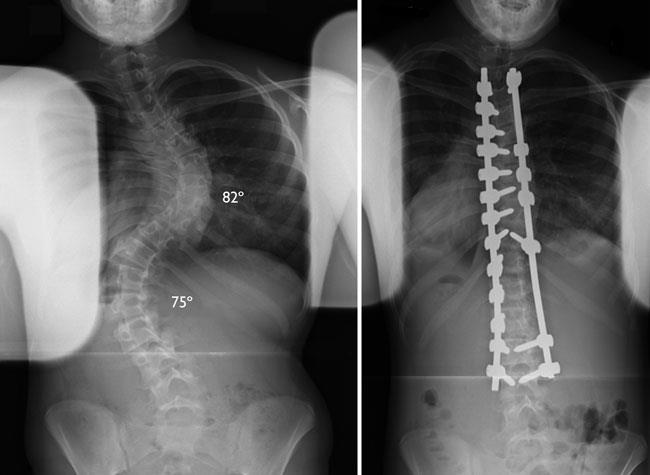

Debe tener presente que la escoliosis o la alteración en la normalidad de la columna respecto a su trayecto la mayoría de las veces no requiere de operación pero si puede necesitar algunos ejercicios físicos que ayudan a a mejorar las molestias producidas. Radiología de la escoliosis. Departamentos de Radiología y Pediatría Facultad de Medicina Pontificia Universidad Católica de Chile. Radiografia de columna vertebral desviada. PDF On Jan 1 2009 Julio Duart and others published Radiología de la columna vertebral Find read and cite all the research you need on ResearchGate. La radiografía es la técnica primaria y principal en el estudio de los trastornos de la alineación de la columna vertebral esto es debido tanto a la claridad y gran utilidad diagnóstica de las imágenes que proporciona como al fácil acceso y rapidez de la exploración. Se trata del nombre más técnico para referirnos a una espalda torcidaEn Clínicas H3 disponemos de los mejores profesionales que estudiarán tu caso de escoliosis o columna desviada y realizarán el diagnóstico más apropiado. La escoliosis ocurre cuando las vértebras de la columna torácica se encuentran desviadas lateralmente giradas formando una C o una S lo que puede afectar la cervical dorsal yo lumbar. Debe tener presente que la escoliosis o la alteración en la normalidad de la columna respecto a su trayecto la mayoría de las veces no requiere de operación pero si puede necesitar algunos ejercicios físicos que ayudan a a mejorar las molestias producidas.